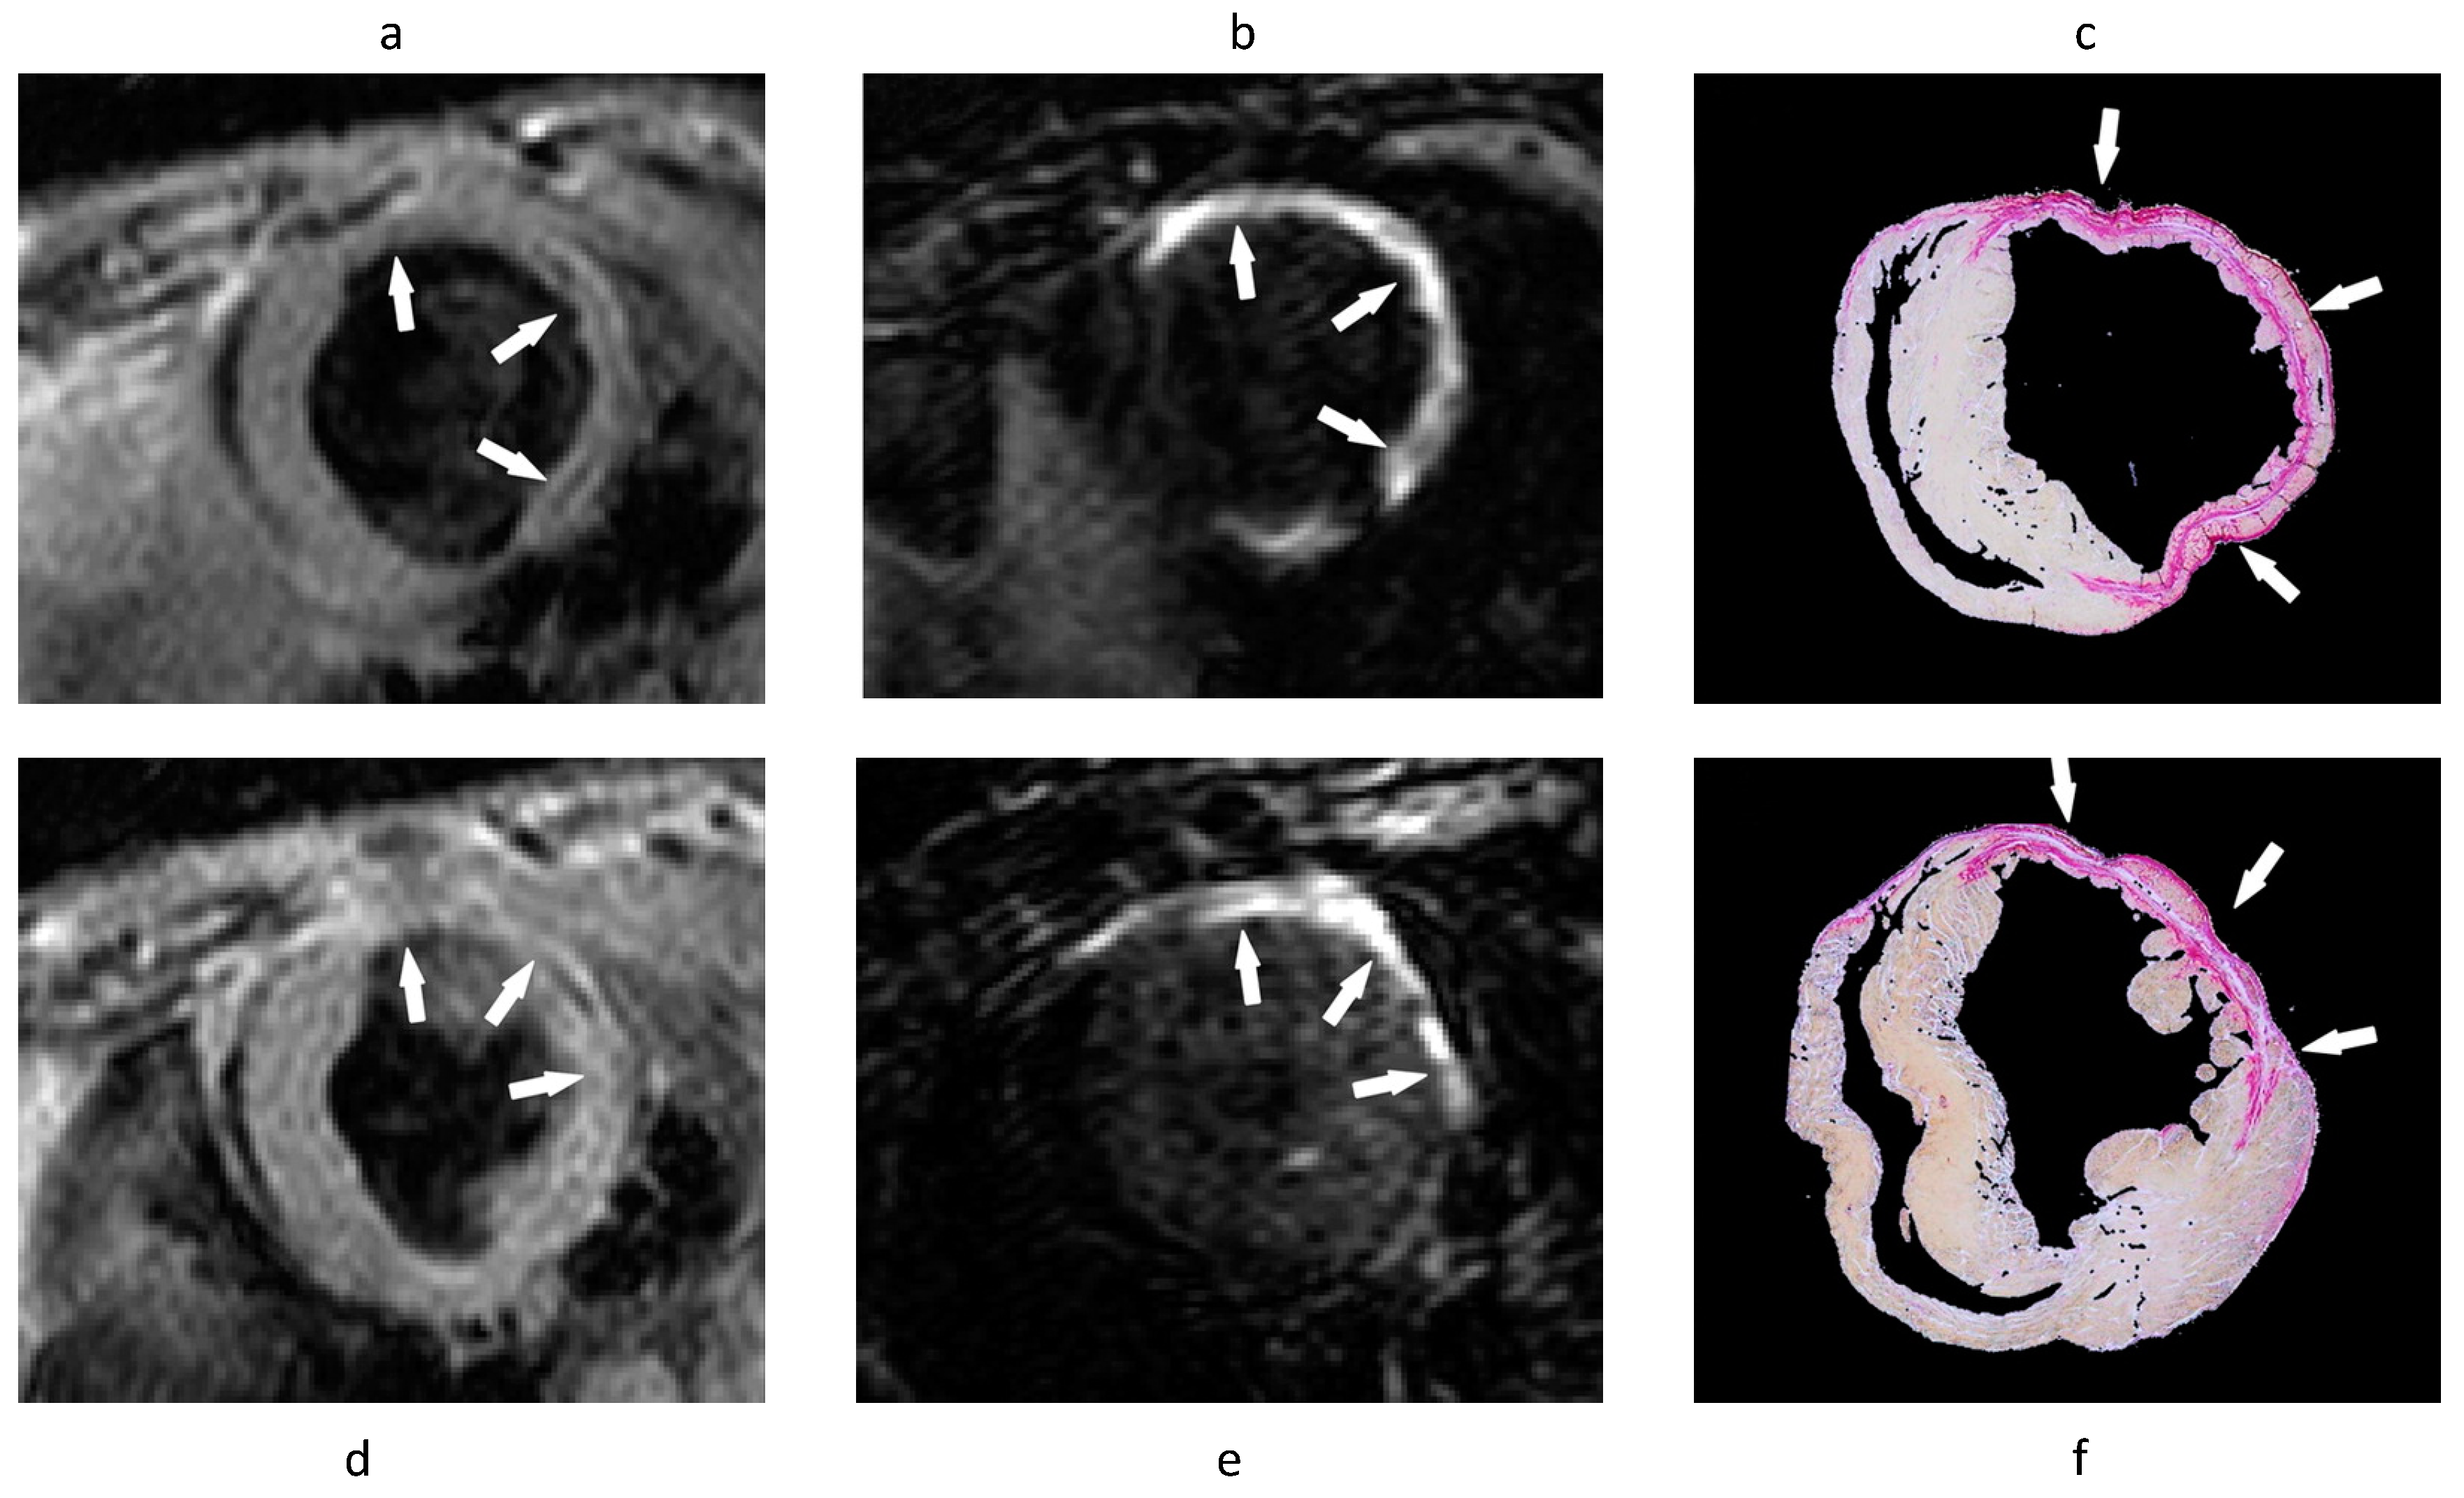

- Helm, P.A.; Caravan, P.; French, B.A.; Jacques, V.; Shen, L.; Xu, Y.; Beyers, R.J.; Roy, R.J.; Kramer, C.M.; Epstein, F.H. Postinfarction myocardial scarring in mice: Molecular MR imaging with use of a collagen-targeting contrast agent. Radiology 2008, 247, 788–796. [Google Scholar] [CrossRef] [PubMed]

- Wildgruber, M.; Bielicki, I.; Aichler, M.; Kosanke, K.; Feuchtinger, A.; Settles, M.; Onthank, D.C.; Cesati, R.R.; Robinson, S.P.; Huber, A.M.; et al. Assessment of myocardial infarction and postinfarction scar remodeling with an elastin-specific magnetic resonance agent. Circ. Cardiovasc. Imaging 2014, 7, 321–329. [Google Scholar] [CrossRef] [PubMed]

- Protti, A.; Lavin, B.; Dong, X.; Lorrio, S.; Robinson, S.; Onthank, D.; Shah, A.M.; Botnar, R.M. Assessment of Myocardial Remodeling Using an Elastin/Tropoelastin Specific Agent with High Field Magnetic Resonance Imaging (MRI). J. Am. Heart Assoc. 2015, 4, e001851. [Google Scholar] [CrossRef]

- Ramos, I.T.; Henningsson, M.; Nezafat, M.; Lavin, B.; Lorrio, S.; Gebhardt, P.; Protti, A.; Eykyn, T.R.; Andia, M.E.; Flögel, U.; et al. Simultaneous Assessment of Cardiac Inflammation and Extracellular Matrix Remodeling after Myocardial Infarction. Circ. Cardiovasc. Imaging 2018, 11, e007453. [Google Scholar] [CrossRef]